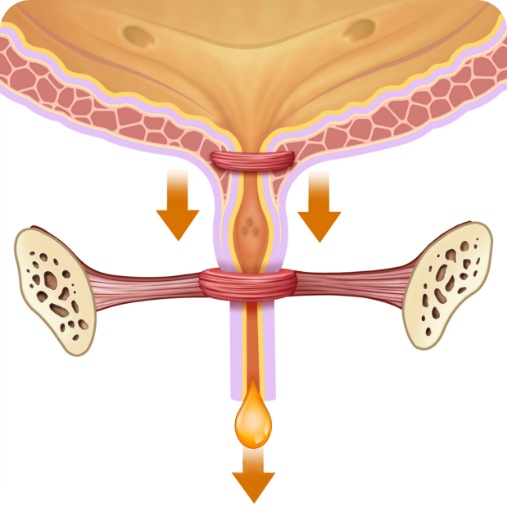

PRZED kuracją:

Słabe mięśnie cewki

PO kuracji:

Mocne mięśnie cewki